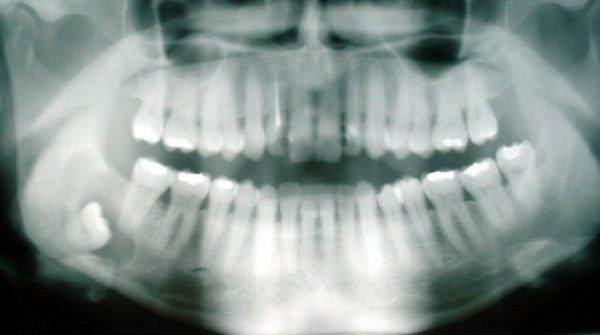

第三个,智齿

智齿是指人类口腔内牙槽骨上最里面的第三颗磨牙,从正中的门牙往里数刚好是第八颗牙齿。由于它萌出时间很晚,一般在16~25岁间萌出,这些牙齿没有什么用处,给我们带来的只有痛苦。智齿是人类进化的残余物,在人类还是洞穴人的时候也许有用。